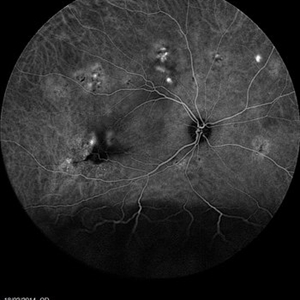

Multifocal Exudative Detachments Due to VKH

May 14 2014 by Avris Romario Diparaja Siahaan

FA a 38-year-old man with multifocal CSR and inferior exudative retinal detachment on both eyes (Harada Syndrome).

Photographer: Avris Romario Diparaja Siahaan, Klinik Mata Nusantara

Imaging device: Heidelberg HRA + OCT Spectralis

Condition/keywords: multifocal central serous chorioretinopathy (CSCR)